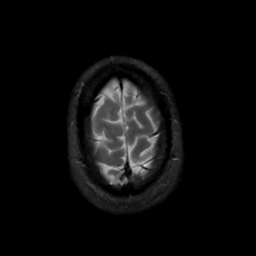

MR Study #8, March 31, 1991 -- Slice #45

[Home][Help][Clinical][Tour 1][Tour 2] Slice 45